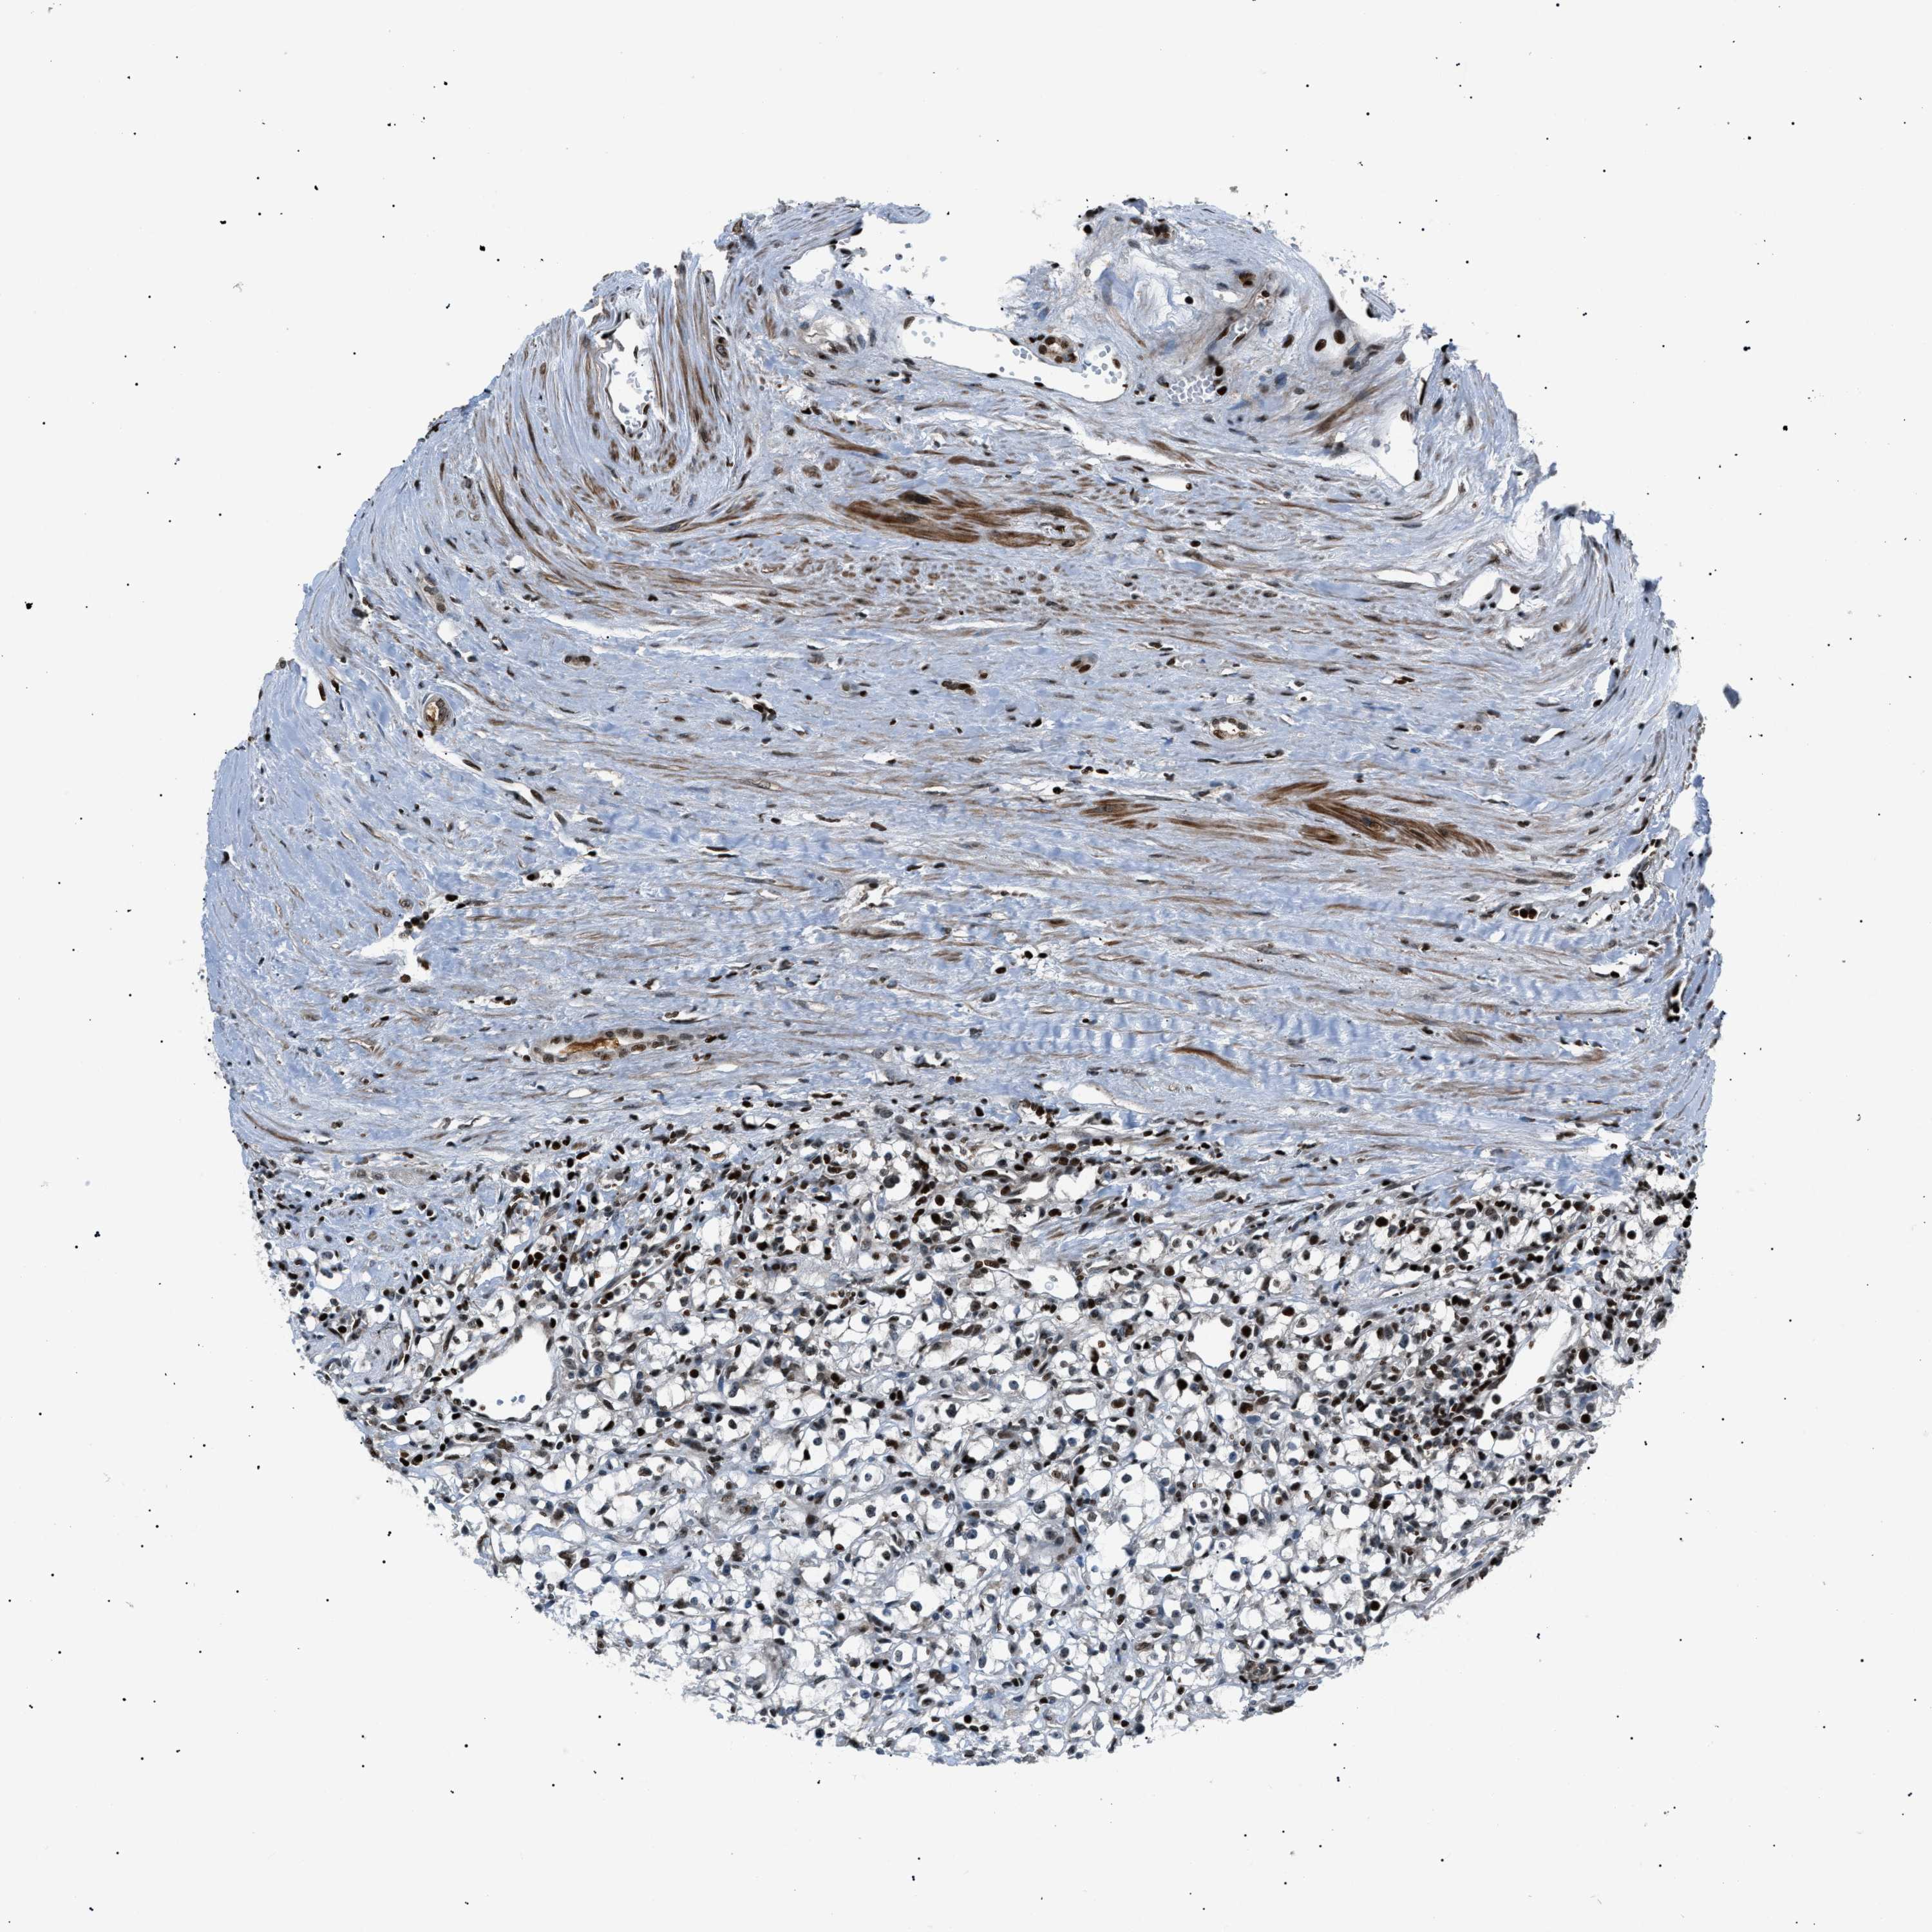

KIDNEY RENAL CLEAR CELL CARCINOMA (TCGA) - Interactive survival scatter ploti

The Survival Scatter plot shows the clinical status (i.e. dead or alive) for all individuals in the patient cohort, based on the same data that underlies the corresponding Kaplan-Meier plots. Patients that are alive at last time for follow-up are shown in blue and patients who have died during the study are shown in red.

The x-axis shows the expression levels (FPKM) of the investigated gene in the tumor tissue at the time of diagnosis. The y-axis shows the follow-up time after diagnosis (years). Both axes are complimented with kernel density curves demonstrating the data density over the axes. The top density plot shows the expression levels (FPKM) distribution among dead (red) and alive patients (blue). The right density plot shows the data density of the survived years of dead patients with high and low expression levels respectively, stratified using the cutoff indicated by the vertical dashed line through the Survival Scatter plot. This cutoff is automatically defined based on the FPKM cutoff that minimizes the p-score. The cutoff can be changed by dragging the vertical line or by entering a cutoff value in the square labeled "Current cut-off".

Under the Survival Scatter plot the p-score landscape (black curve; left axis) is shown together with dead median separation (red curve; right axis). Dead median separation is the difference in median mRNA expression between patients who have died with high and low expression, respectively. It is calculated as follows: median FPKM expression of dead patients with high expression - median FPKM expression of dead patients with low expression. This is intended to aid the user in visually exploring custom cutoffs and the associated p-scores and dead median separation.

Individual patient data is displayed and can be filtered by clicking on one or more of the category buttons on the top of the page. Categories describing expression level and patient information include: high, low, alive, dead, female, male and tumor stages. The scale of the x-axis can be toggled between linear and log-scale by clicking on the "x log" button. Mouse-over function shows TCGA ID, patient information and mRNA expression (FPKM) for each patient.

& Survival analysisi

Kaplan-Meier plots summarize results from analysis of correlation between mRNA expression level and patient survival. Patients were divided based on level of expression into one of the two groups "low" (under cut off) or "high" (over cut off). X-axis shows time for survival (years) and y-axis shows the probability of survival, where 1.0 corresponds to 100 percent.

PRKX is potential prognostic, high expression is favorable in Kidney Renal Clear Cell Carcinoma (TCGA)

Best expression cut offi

: 9.13